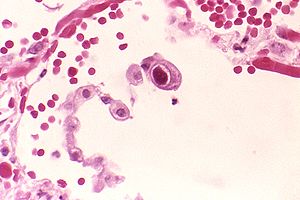

🧫 سیتومگالوویروس (CMV) در هفته یازدهم بارداری

بیشتر بزرگسالان در طول زندگی خود یکبار به CMV مبتلا میشوند و معمولاً متوجه آن نمیشوند، زیرا علائمش شبیه سرماخوردگی خفیف است (تب، گلودرد، خستگی، ورم غدد).

اما اگر در سهماهه اول بارداری برای نخستین بار به CMV مبتلا شوید، احتمال خطر برای جنین افزایش مییابد. این ویروس میتواند باعث کاهش شنوایی، مشکلات بینایی یا عقبماندگی ذهنی جنین شود.

برای پیشگیری:

– هنگام تعویض پوشک کودک، حتماً دستکش بپوشید یا دستها را بشویید.

– از اشتراک وسایل شخصی با کودکان یا بیماران خودداری کنید.

اگر سابقه ابتلا به CMV دارید، احتمال آسیب به جنین بسیار کمتر است.